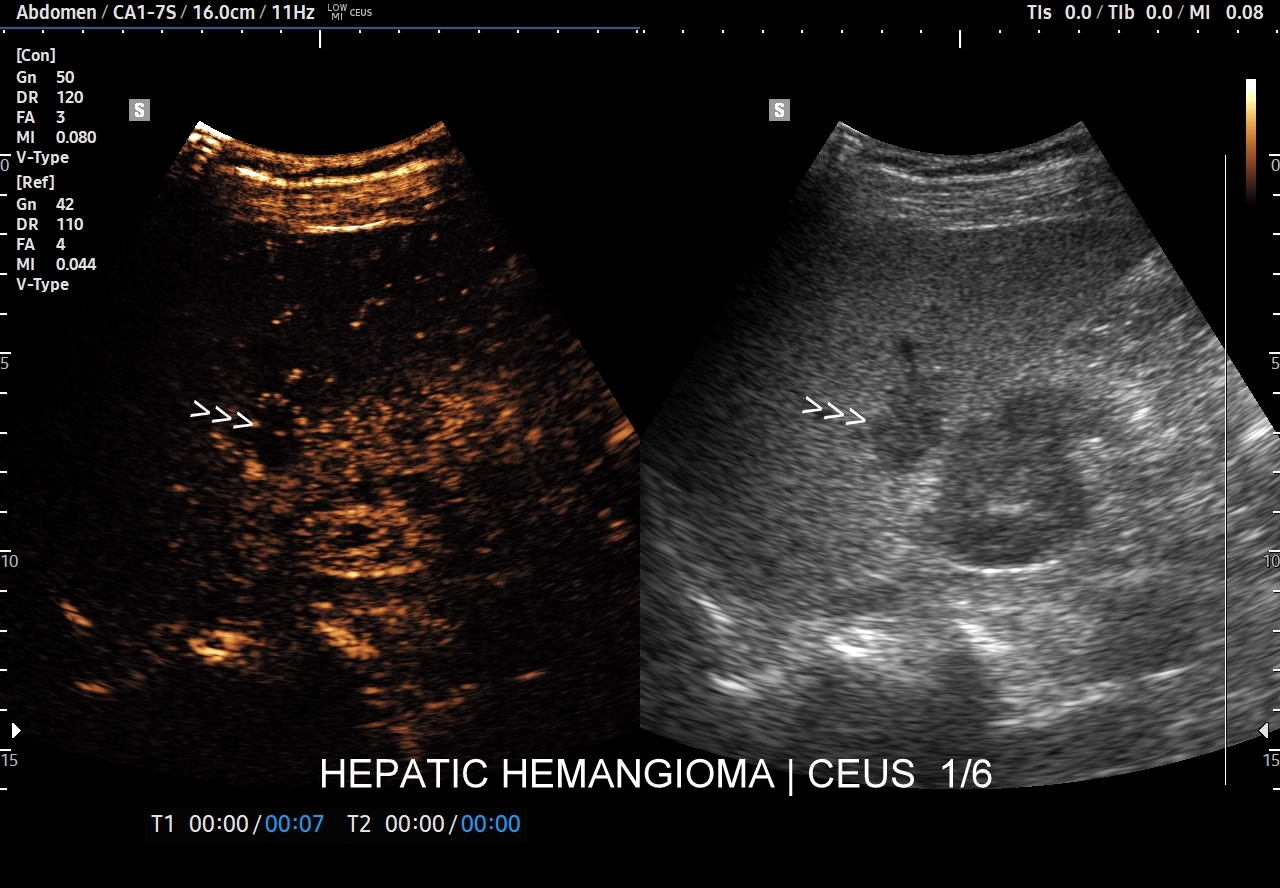

Najbardziej charakterystyczną cechą naczyniaka wątroby w badaniu CEUS jest jego wypełnianie w postaci guzkowej (ang. peripheral nodular enhancement) od obwodu ku centrum zmiany (ang. centripetal). Szybkość wypełniania bywa różnorodna, może być powolna lub szybka. W przypadku szybkiego wypełniania (tzw. flash-filling), w celu wykazania charakterystycznego centrypetalnego wypełniania niezbędna może być postprocessing’owa analiza poklatkowa zapisanego nagrania badania. W fazie późnej naczyniak wątroby pozostaje izowzmocniony lub hyperwzmocniony w stosunku do natywnego miąższu wątroby.